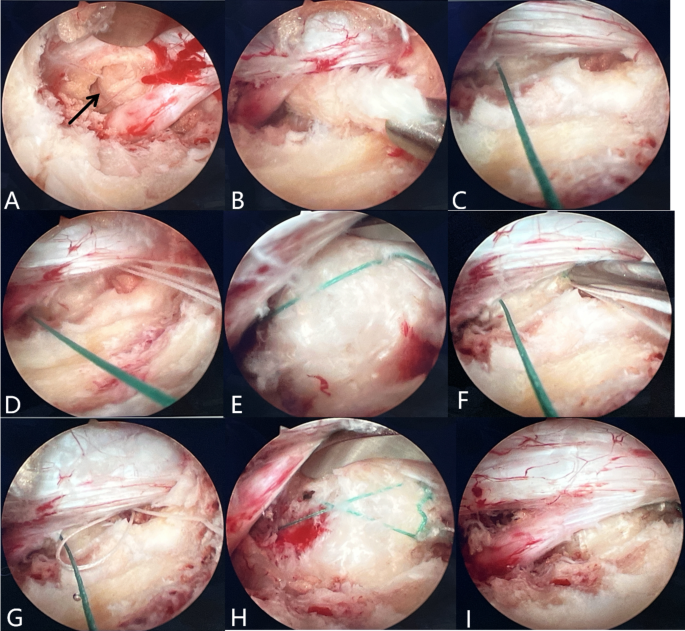

The surgical procedure of the X-shaped bone-anchoring annulus fibrosus suture technique under arthroscopic-assisted uni-portal spinal surgery. (A) Exposure of the protruding nucleus pulposu. (B) Excision of the nucleus pulposus reveals the damaged annulus fibrosus. (C) Penetration of the first stitch into the inferior vertebral body. (D,E) Penetration of the second stitch at the lateral section of the annulus fibrosus and tightening with the first stitch to tie a square knot. (F–H) Anchor the first stitch diagonally to one side of the vertebral body and then sew another stitch. (I) No visible compression of the nerve root after suturing.